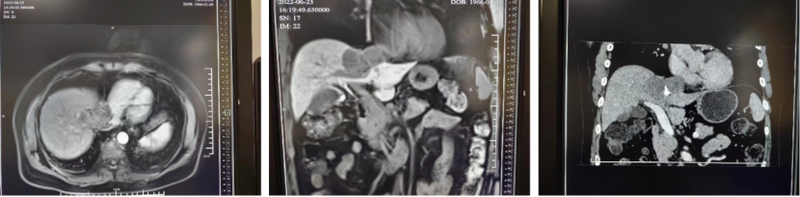

近日,為一位肝癌晚期患者進(jìn)行了挽救性介入治療。這位患者的病灶位于第二肝門,曾在外院接受過2次介入治療。但歷時一年,病灶進(jìn)展明顯,已經(jīng)侵犯肝中靜脈,壓迫下腔靜脈及右心房,且肺部有多發(fā)轉(zhuǎn)移。同時,MR和CT檢查顯示病灶血供較少,預(yù)計再次介入治療效果欠佳。此時,由于疾病分期已晚,且病灶部位特殊,又在經(jīng)歷2次介入治療后發(fā)生進(jìn)展,患者的生存質(zhì)量已被嚴(yán)重影響。在無奈中,患者四處輾轉(zhuǎn)來到我院。面對如此情況,我們選擇對患者進(jìn)行了挽救性介入,以幫助患者延長生存期,改善生活質(zhì)量。幸運的是,術(shù)中造影顯示病灶血供比術(shù)前評估的好。因此,盡管手術(shù)過程艱辛,但是手術(shù)治療效果還是令人滿意的。術(shù)后第四天,CT平掃顯示病灶碘油沉積致密、完整。術(shù)后第五天復(fù)查MR,顯示病灶已基本上完全壞死,達(dá)到了預(yù)期的治療目標(biāo)。健康所系,性命相托。在頑強(qiáng)的生命面前,再一次感到我們要保持敬畏,竭盡全力,爭取每一次救治都做到極致。不輕言放棄,奇跡就會發(fā)生。分享本案例,謹(jǐn)與大家共勉!